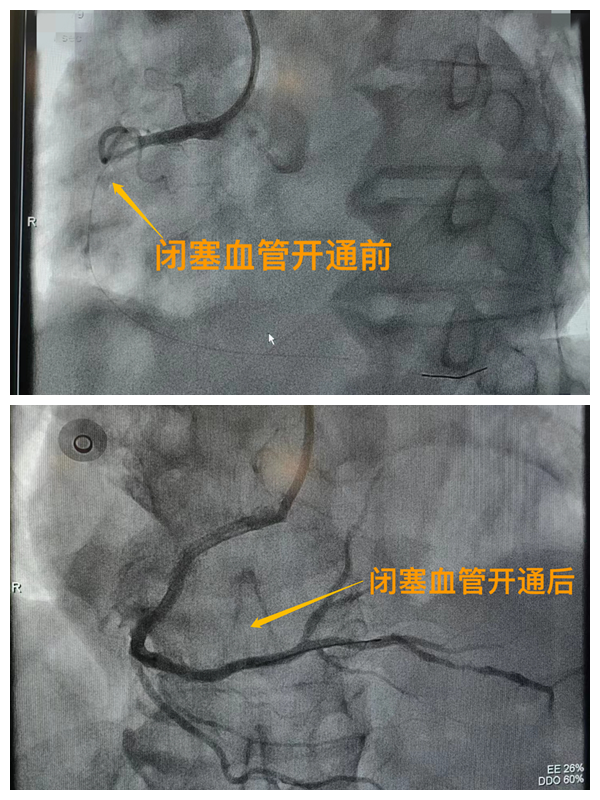

活動開始前,院長王瑾對現(xiàn)場群眾進行了健康科普宣講,她以近期醫(yī)院救治的多例急性心肌梗死患者的癥狀、發(fā)展、急救、手術(shù)、康復(fù)全流程情況為例,向小區(qū)群眾講述了心梗的發(fā)病癥狀和院前急救注意事項,以及要及時通過120送至專業(yè)的胸痛中心開展科學(xué)、規(guī)范的急救手術(shù)的必要性,講述了心梗患者轉(zhuǎn)危為安的全過程,得到了廣大群眾的共鳴與好評。

市二院胸痛中心于2021年12月23日通過中國胸痛中心認(rèn)證,成為國家級胸痛中心,先后開展了冠心病的介入診療、心律失常的心內(nèi)電生理檢查及射頻消融治療、永久起搏器植入、先天性心臟病的介入封堵及臨時起搏器植入、主動脈內(nèi)球囊反搏治療等,完成心臟介入手術(shù)3000余例。多次創(chuàng)造從入院至行急診介入手術(shù)開通血管(入門-導(dǎo)絲通過)30分鐘以內(nèi)記錄,極大保證了患者的生命安全,提高了預(yù)后質(zhì)量,挽救了眾多急性心?;颊叩纳?。(尹紅婭       張   靜)